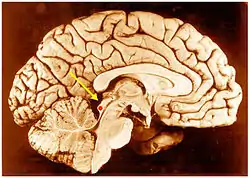

Inferior colliculus (red dot) in human brain, sagittal section.

Inferior colliculus